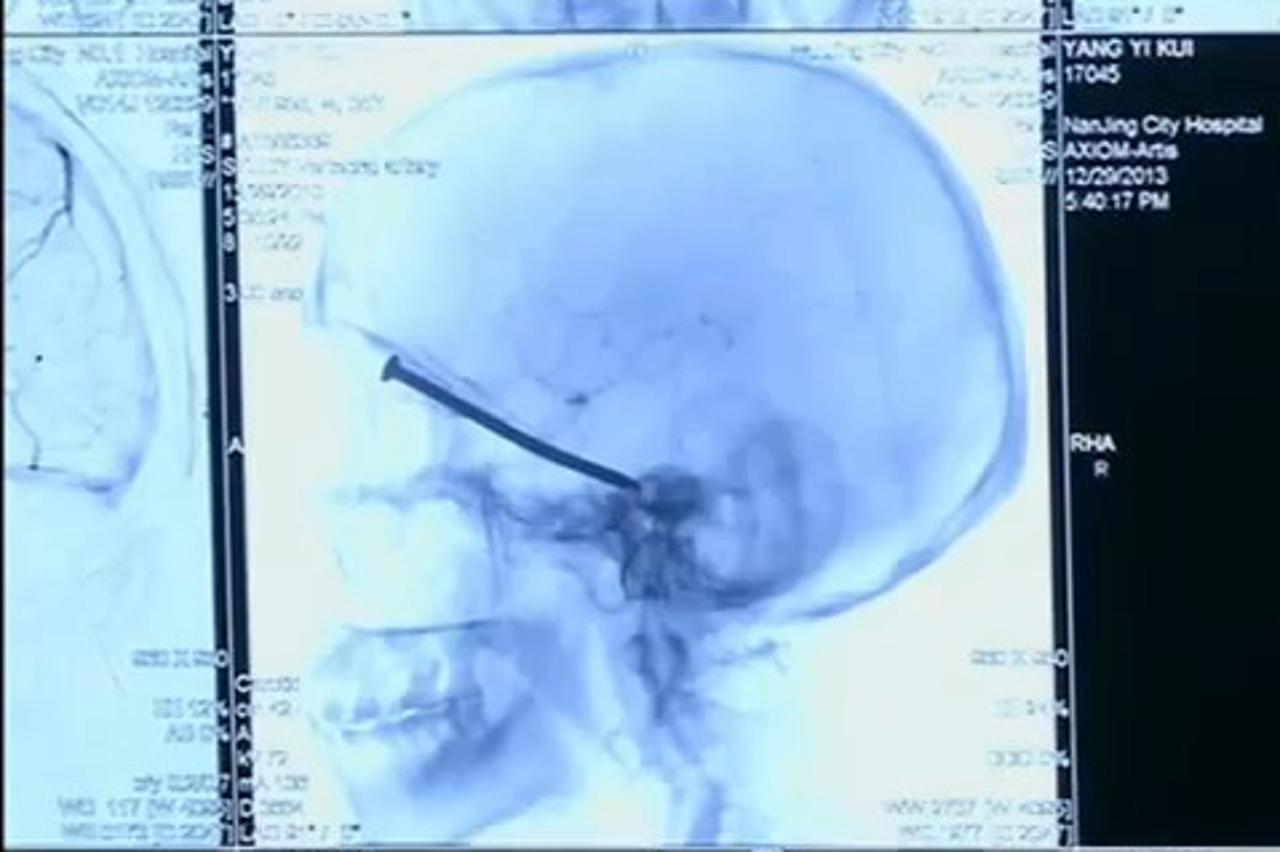

NESVAKIDAŠNJI SLUČAJ Liječnici muškarcu (66) iz glave izvadili čavao dužine deset centimetara Ovo je nešto što se rijetko kada, pa skoro i nikada, ne sretne u karijeri, rekao je kirurg

Video sadržaj Nije ozlijeđen Čavao dug 8 cm probio mu oko i završio u lubanji! Muškarac je ispričao kako nije osjetio da mu je čavao prodro u lubanju kroz očnu duplju sve dok nije počeo osjećati mučninu.